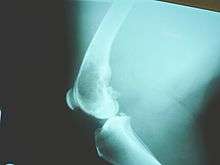

Family physicians and orthopedists rarely see a malignant bone tumor (most bone tumors are benign). The route to osteosarcoma diagnosis usually begins with an X-ray, continues with a combination of scans (CT scan, PET scan, bone scan, MRI) and ends with a surgical biopsy. A characteristic often seen in an X-ray is Codman's triangle, which is basically a subperiosteal lesion formed when the periosteum is raised due to the tumor. Films are suggestive, but bone biopsy is the only definitive method to determine whether a tumor is malignant or benign.